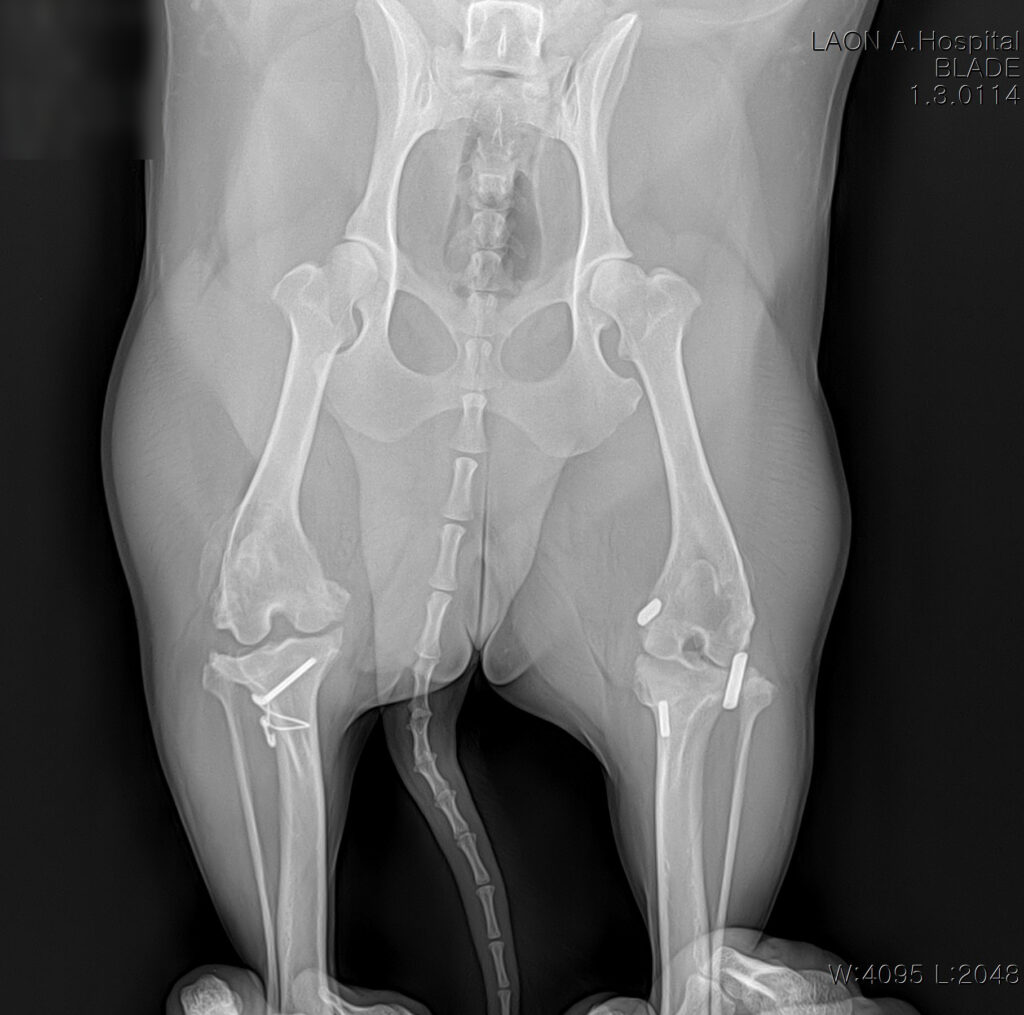

환자는 평소 활발하고 산책을 좋아하는 12kg의 중형견입니다. 과거 우측 슬개골 탈구 수술, 좌측 십자인대 단열로 낭외고정수술을 받은 이력이 있었지만 이후에는 꾸준히 양호한 보행을 유지해오다 최근 오른쪽 뒷다리에 체중을 싣지 못하고 절뚝거림이 심해져 내원하였습니다.

십자인대 단열 진단

방사선 촬영 결과, 우측 십자인대 완전 파열과 무릎 관절의 퇴행성 관절염 소견이 함께 확인되었습니다. 보행 시 무릎이 흔들리며 통증이 동반되는 상태로, 정상적인 활동을 위해 TPLO 수술이 필요했습니다.

수술 후 방사선 사진/ 출처: 라온동물메디컬센터